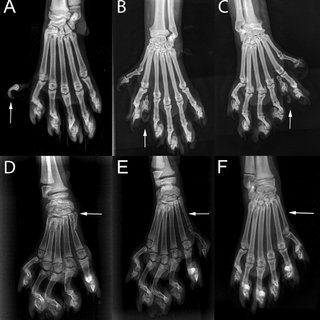

Vanlige problemer og ting man skal være oppmerksomme på hos katter med ekstra tær/klør:

– Tredeputene kan gnage på hverandre

– Klørne kan være skjevt plassert og gnage i huden/poten

– Leddene kan være vridde, noe som kan være smertefullt

– Om det ikke er plass til kattens ekstra tær “former de seg til plassen”, noe som kan gi skjeve ledd.

– Ekstra tær med klør kan henge seg fast ved aktivitet og skades eller rives opp.

– Kloproblemer som inngrodde eller forgrodde klør.

Når putene og klør ligger “hultertilbulter” på poten, hvordan oppleves dette for katten?, har de leddsmerter, muskel eller nerve ubehag. Katten skal tross alt gå på disse potene gjennom hele livet. Vet vi at katten gjennom hele livet vil ha smertefrie poter?